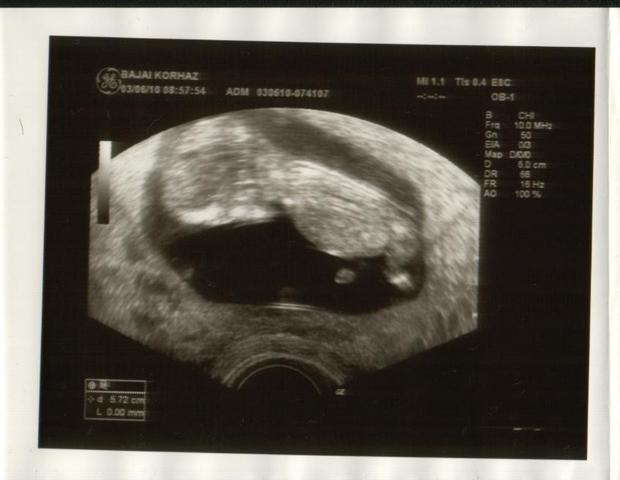

Édes kisbabám

Édes kisbabám